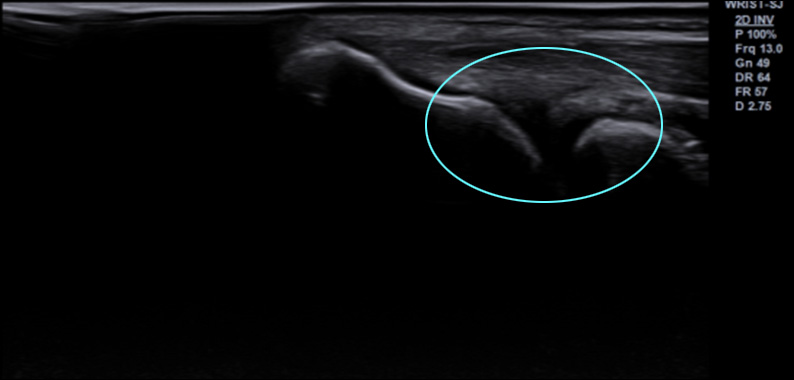

조직재생 유도 물질로 잘 알려진 PDRN과

자하거(태반)를 환자별 맞춤 배합하여 초음파를 보며

손·팔꿈치 통증 병변에 주입